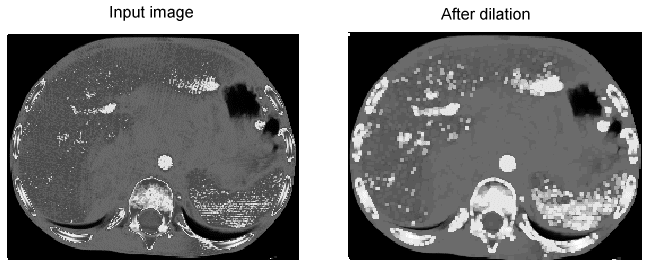

Dilation

Dilation enhances the bright features of the image while suppressing the darker features:

Image Processing Morphology Theory Grey Scale Morphology Example Dilation